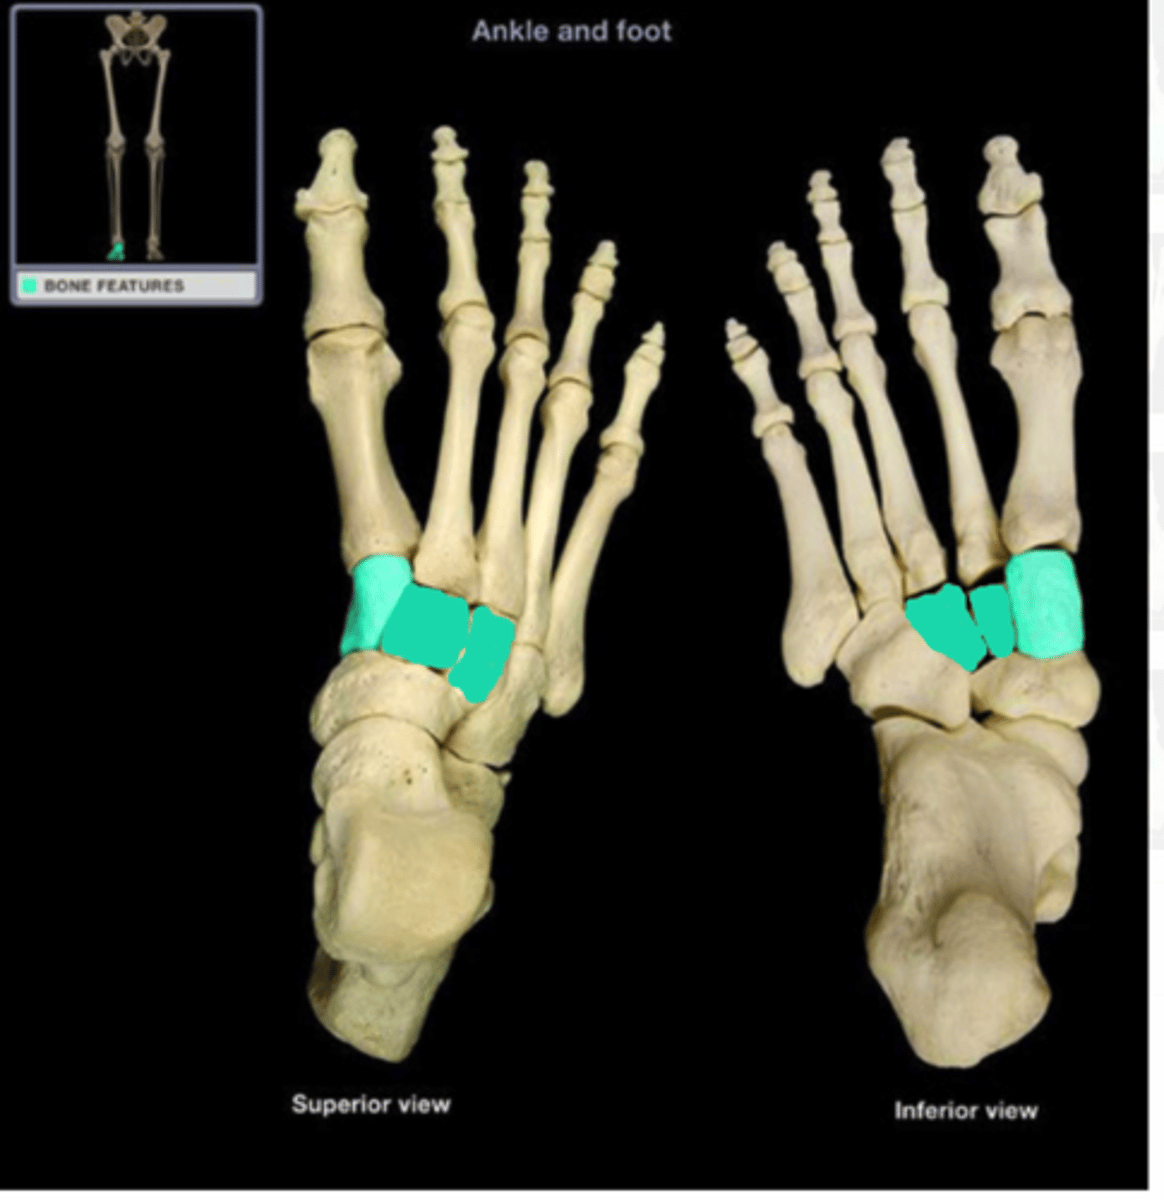

phalanges

metatarsals

tarsals

navicular

cuneiforms

cuboid

transverse arch

longitudinal arch